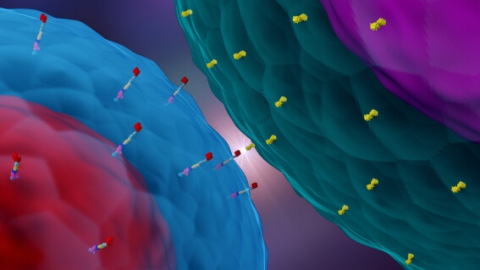

Research & Clinical Trials

Research & Clinical TrialsResearchers Open Phase I Clinical Trial of Cryoablation with Keytruda

Memorial Sloan Kettering Cancer Center in New York City has opened a novel clinical trial that combines the immunotherapy drug Keytruda with… -

Research & Clinical Trials

Research & Clinical TrialsNew Opdivo/Yervoy Mesothelioma Clinical Trial Begins Soon

A novel clinical trial involving the immunotherapy combination of Opdivo and Yervoy will open soon in Chicago. The goal is to study the… -